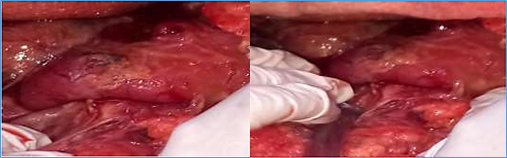

1. Hemoperitoneum of 2500ml between clots and non-coagulated blood (Figure 1).

Figure 1 Manual exposure of the bleeding bed in the upper quadrants.